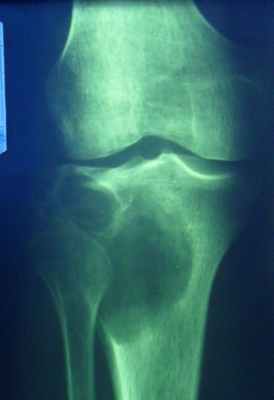

Специфическая воспалительная деструкция — это туберкулез, сифилис и др, при которых костная ткань замещается специфической гранулемой. Деструкция при этих заболеваниях отличается по локализации, форме, размерам и характеру очагов, а также особенностью реакции со стороны окружающей костной ткани и надкостницы. Очаг деструкции при туберкулезе, как правило, располагается в губчатом веществе эпифиза, он небольших размеров, округлой формы без или с очень незначительной склеротической реакцией вокруг. Реакция надкостницы чаще отсутствует.